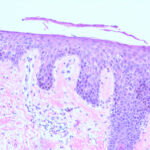

Histopathology. The earliest change consists of acantholysis in the upper epidermis, within or adjacent to the granular layer, leading to a subcorneal bulla in some instances . More commonly, enlargement of the cleft leads to detachment |

of the stratum corneum without bulla being seen. The number of acantholytic keratinocytes is usually small, often requiring a careful search to identify them. Secondary clefts may develop, leading to detachment of the epidermis in its mid level. These clefts may extend to above the basal layer, rarely giving rise to limited areas of suprabasal separation. In the setting of a subcomeal blister, dyskeratotic granular keratinocytes are diagnostic for this disorder. Eosinophilic spongiosis may be prominent with intraepidermal eosinophilic pustules. Thus, the histologic features of pemphigus foliaceus may have three pattems: {a} eosinophilic spongiosis; {b} a subcorneal blister, often with few acantholytic keratinocytes; and {c} a subcorneal blister with dyskeratotic granular keratinocytes , diagnostic of this disorder. The character of the inflammatory infiltrate is variable and depends on the age of the lesion, whether a blister is present, whether the superficial portion of the epidermis has been detached, and whether there is impetiginization or necrosis of the blister roof. |